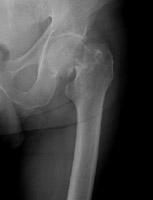

- Click on the image for a larger versionDAP radiograph of the right hip. This shows a Garden III fracture of the proximal femur.